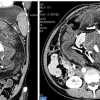

17년간 ‘자신의 쌍둥이’를 뱃속에 품고 산 印소녀 사연